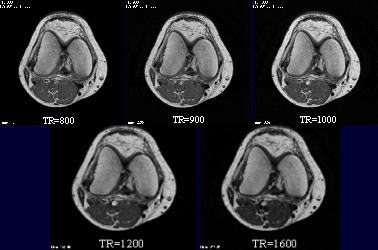

| 幚尡偦偺俀丗TR忦審専摙 TI傪俇侽侽偵屌掕偟偰TR傪怳傝丄奺僒儞僾儖偺怣崋抣傪應掕偟偨丅 TI=600偵屌掕偟丄TR傪曄壔丅乮偦偺懠忦審偼 I偺幚尡偲摨偠乯  |

| 幚尡偦偺俀丗TR忦審専摙 TI傪俇侽侽偵屌掕偟偰TR傪怳傝丄奺僒儞僾儖偺怣崋抣傪應掕偟偨丅 丂丂丂丂丂丂丂  |